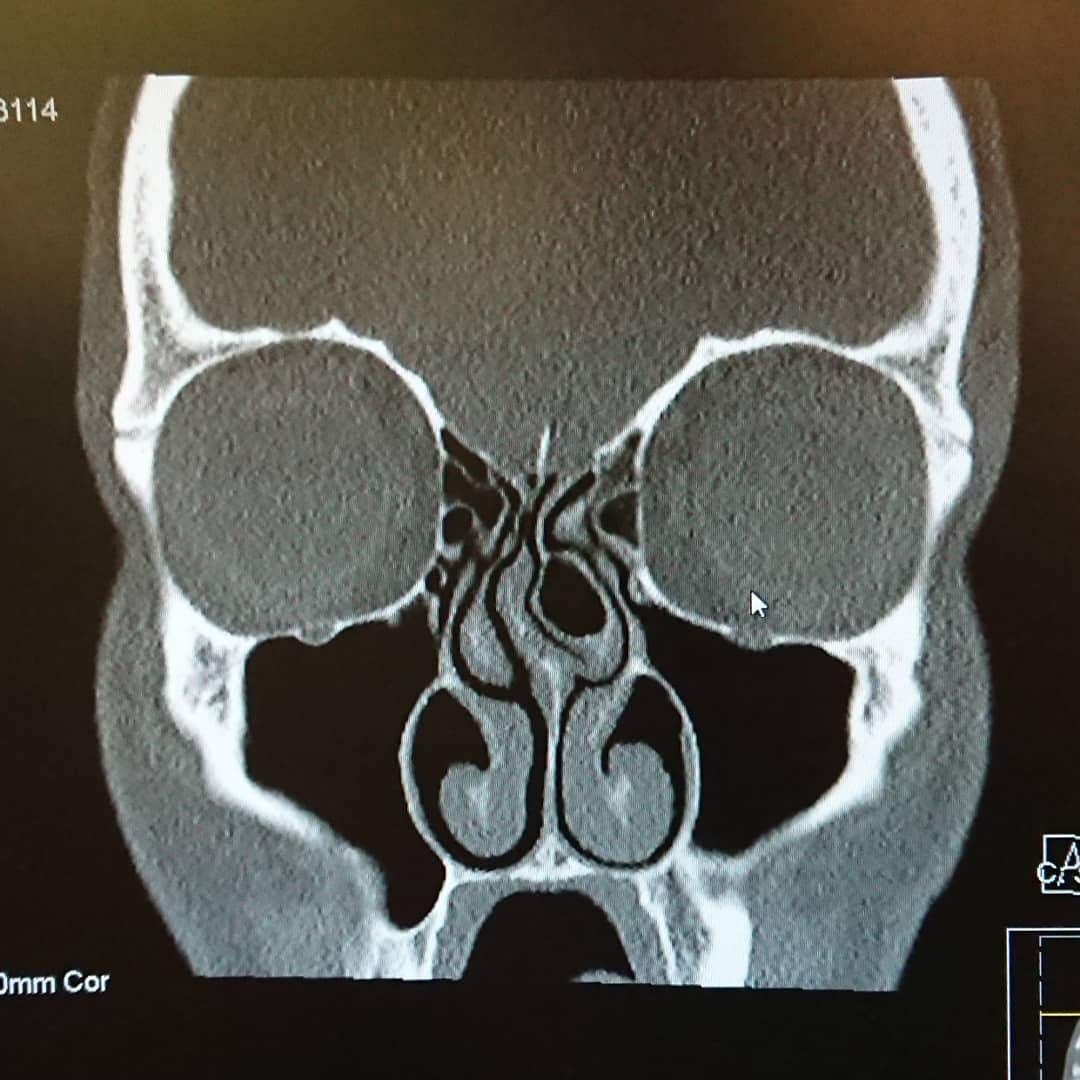

The cyclocross season is drawing to a close so it’s time for all those end-of-season blogs, photo montages and messages of thanks to sponsors! I feel I have a good excuse to write a season wrap-up blog (or two) this year though. Following surgery last week, I’m not fit to do anything else! I am currently sitting at home on the sofa, intermittently snorting/hacking up clods of blood and gore from my sinuses.

Everyone has to deal with illness and stress. I’m no different but this year it all got a bit too much. I missed the 2018 National Championships with a flu-like illness, which then turned in to sinusitis, resulting in weeks off work and keeping me off my bike until March. In my line of work, there’s no one to do it for me while I’m away so, although I get paid (I realise I’m very fortunate here), it’s not great for career progression. General joie de vivre takes a hit too, to put it mildly.

Things turned around after seeing a sinus specialist who advised that, although I may feel terribly fatigued, I wouldn’t be doing myself any harm by going out and smashing it on my bike, and it would actually make me feel a lot better. Indeed it did! Although I’m sure my performance has been somewhat limited by recurrent infections in my sinuses throughout the year, I’ve got even more enjoyment out of my riding than ever I think.

- I’ve just had surgery on my sinuses and will feel amazing again soon.